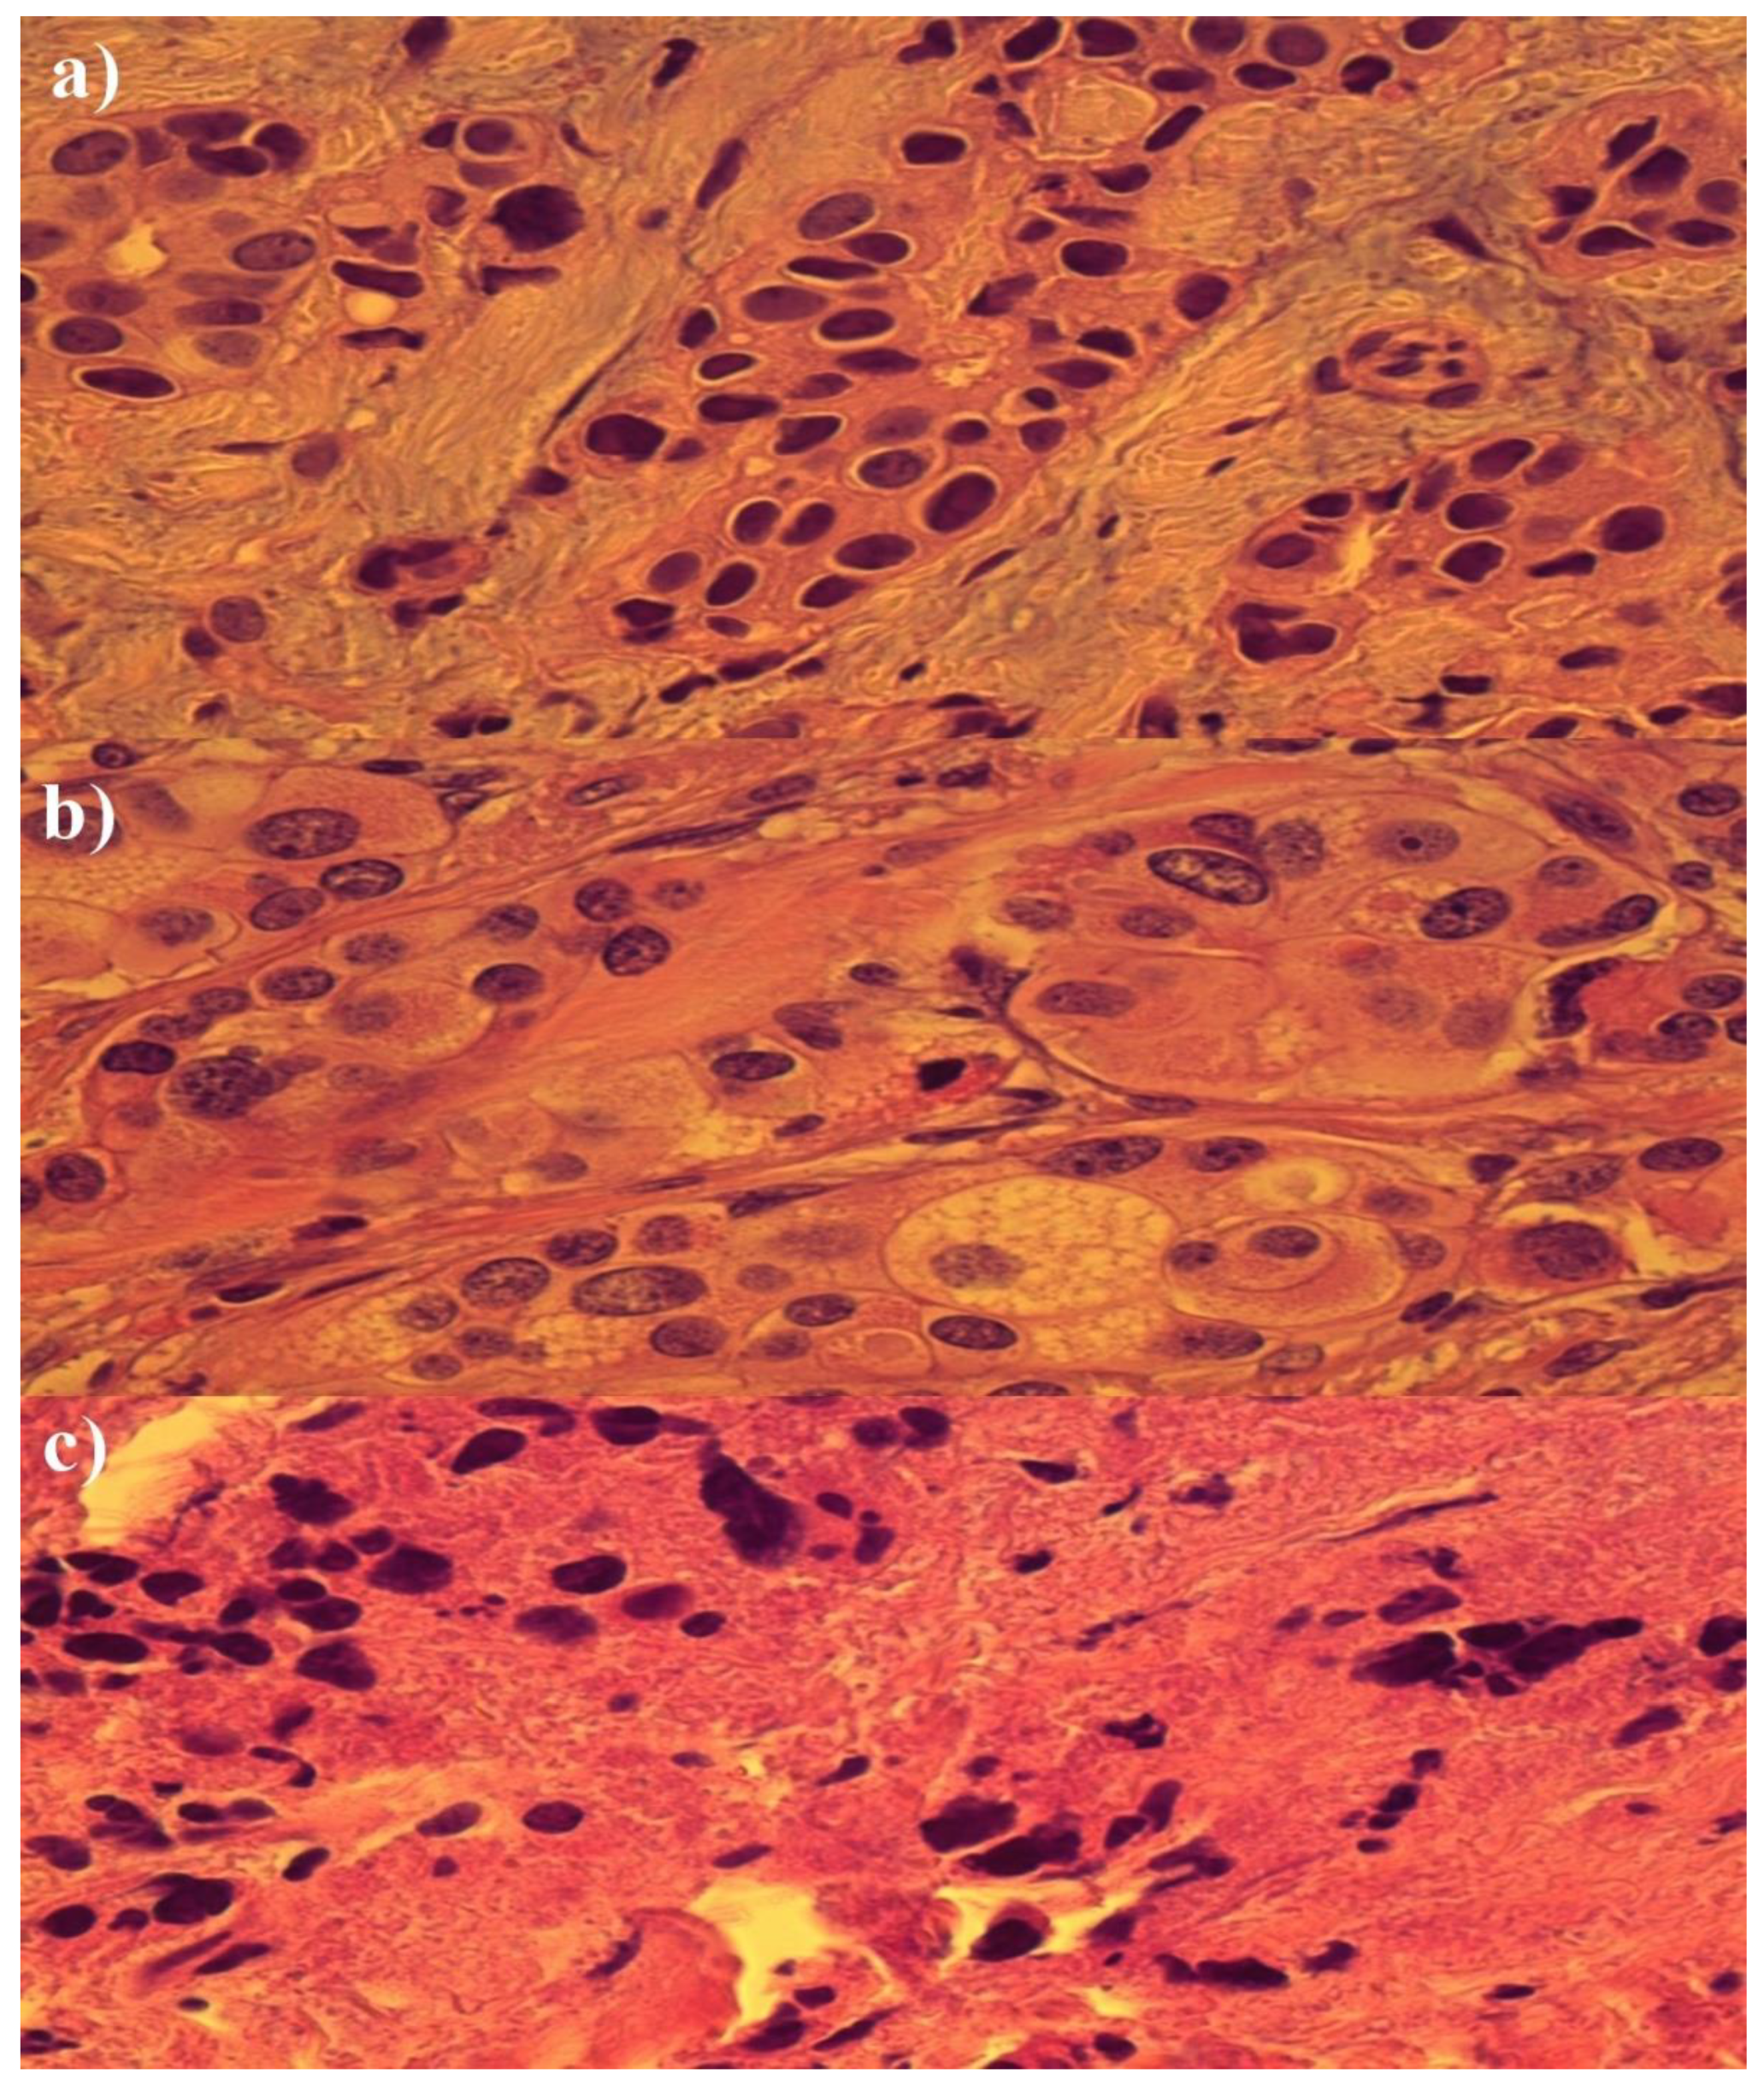

3. Results